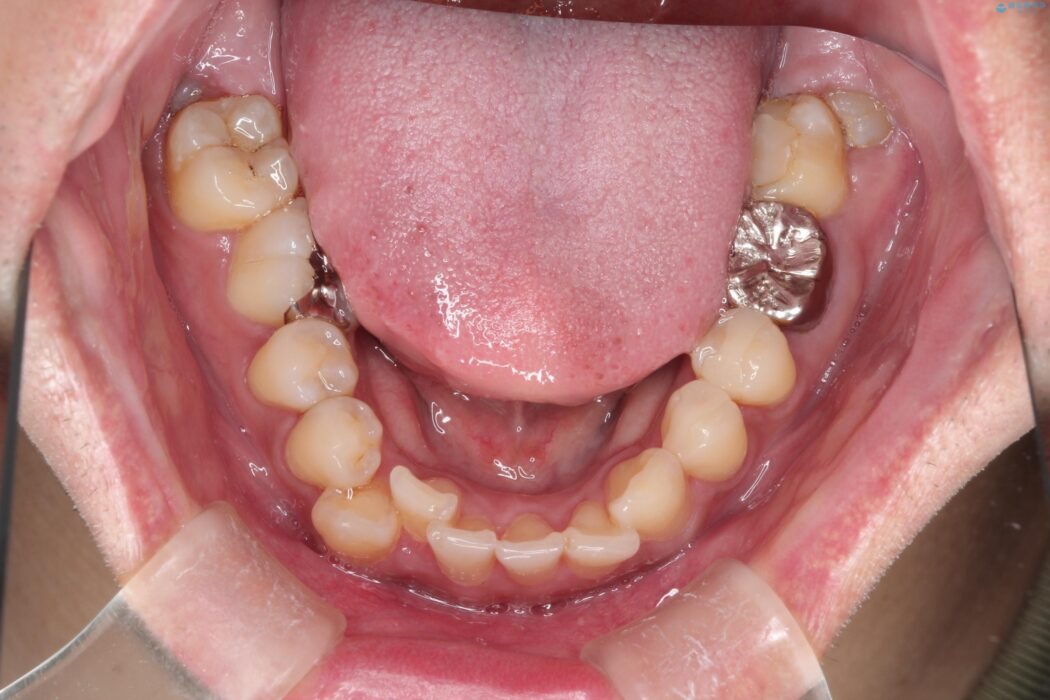

目立つ八重歯と下の歯の凸凹を治したい

右上の八重歯と、下の歯の凸凹を治したいとご来院されました。

上顎右側第一小臼歯と下顎右側第一小臼歯を抜歯しワイヤー矯正を行いました。